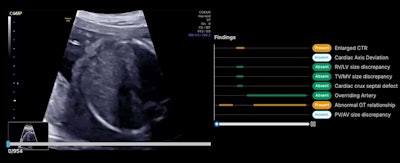

Example of an ultrasound exam being evaluated through an AI system. Researchers found that AI assistance boosted CHD performance among ob/gyns and MFMs reading ultrasound exams.Mount Sinai West

The AI system analyzes grayscale 2D ultrasound exams and detects eight morphological findings associated with severe CHDs. The team used a dataset of 200 ultrasound exams from 11 centers in two countries, with 100 exams having at least one suspicious finding. The researchers also noted that these exams were not used to train the AI system. A panel of experienced fetal cardiologists provided ground truth analysis.